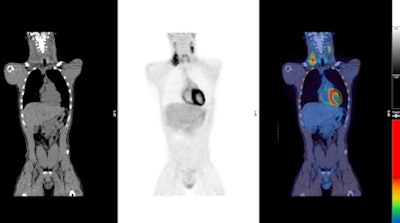

PET/CT images show a Hodgkin's lymphoma patient with inadequate response to treatment or "positive" PET scan after chemotherapy treatment. There was high uptake in lymph nodes on both sides of the neck prior to treatment (above) with persistent high uptake in the right neck after treatment; Deauville score 5 (below). The Deauville criteria is a five-point scoring system used to calculate uptake in PET images. A score of 5 would indicate the greatest amount of uptake. Physiological uptake is seen in the bladder.Follow-up research